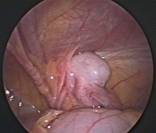

Torsion Testis (Pre and Per operative photo)